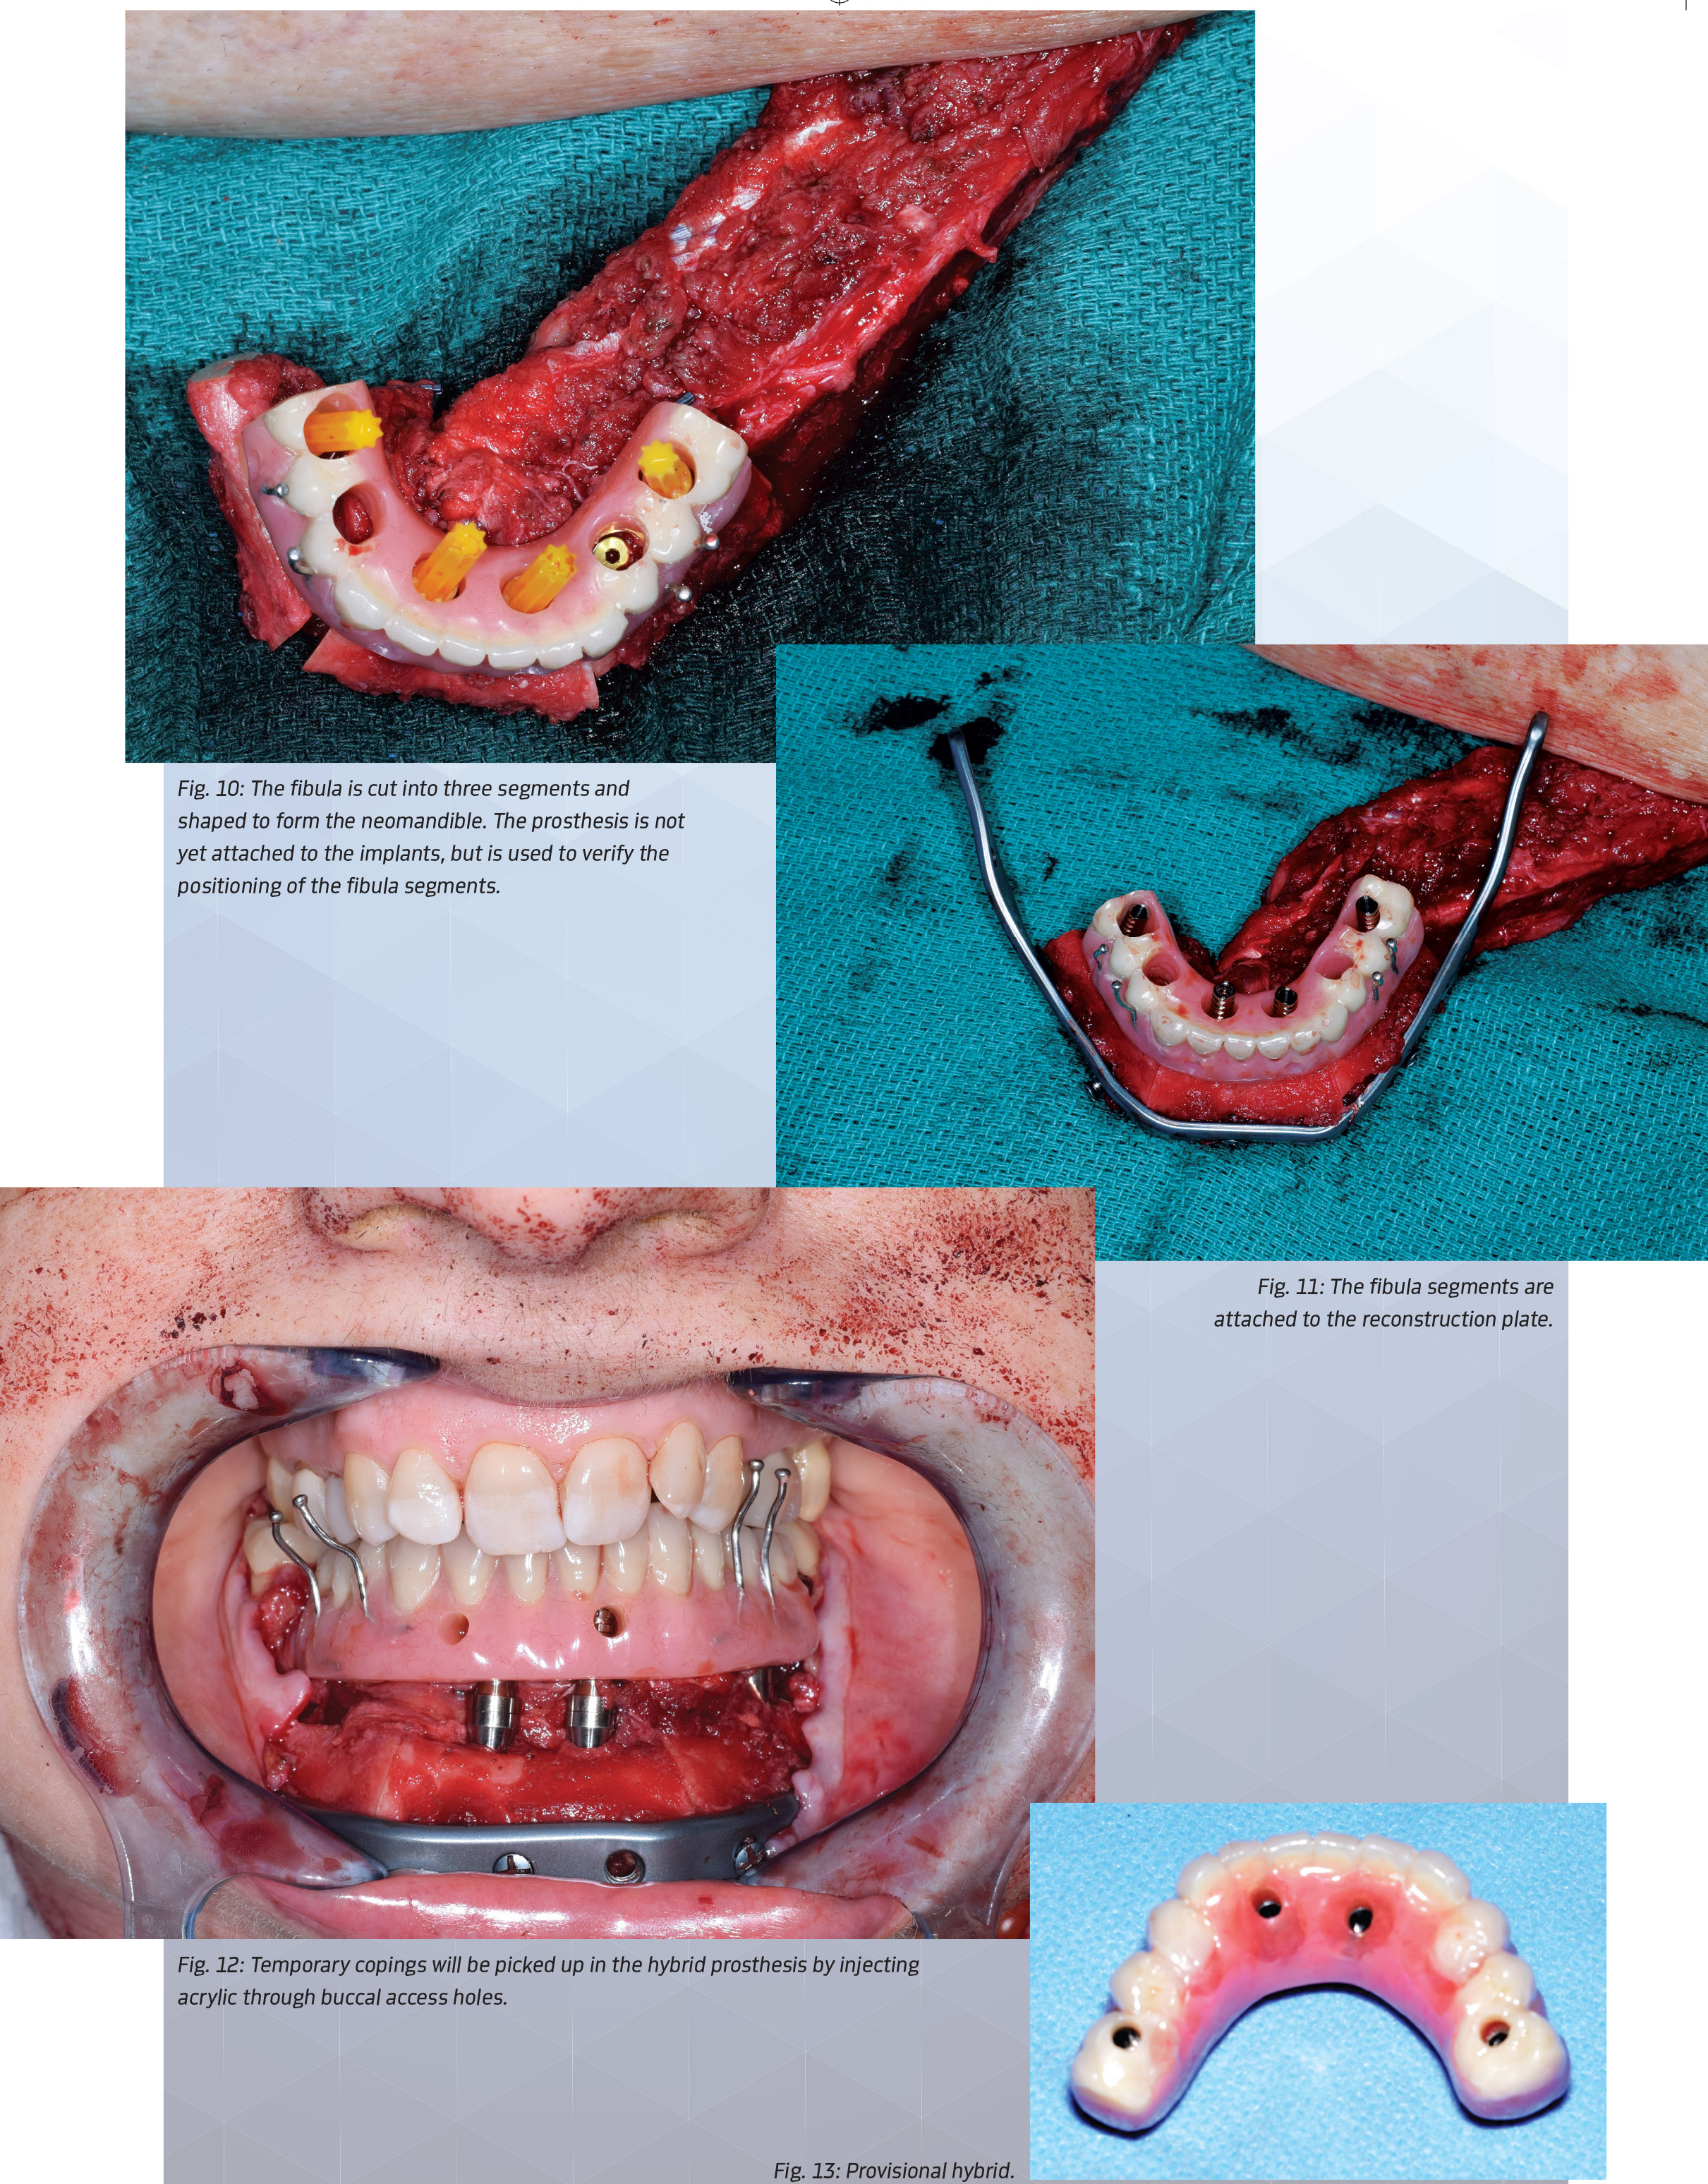

Implants were placed through the inferior border of the fibula for bicortical stabilization. The fibula cutting guide was then used to make closing ostectomies on the fibula to create the curvature of the neomandible (Fig. 10). The three fibula segments were attached to a custom-milled plate while using the hybrid prosthesis as a template to ensure the implants emerged through the planned access opening (Fig. 11).

The fibula vessels were ligated and divided to free the flap from the leg. The fibula was plated to the remaining mandible while verifying that the implant temporary copings still emerged through the occlusal access holes while the teeth were in occlusion. The temporary copings were picked up in the prosthesis by injecting acrylic through the buccal access holes while holding the jaws in proper occlusion (Fig. 12).

The mandibular second molars were preserved up to this point to serve as a vertical stop, although they would be removed later in surgery. The prosthesis was removed and passed off to a back table for the dental lab staff to finalize the hybrid prosthesis (Fig. 13).

Building a Mandible Figure 10: The fibula is cut into three segments and shaped to form the neomandible. The prosthesis is not yet attached to the implants, but is used to verify the positioning of the fibula segments. Figure 11: The fibula segments are attached to the reconstruction plate. Temporary copings will be picked up in the hybrid prosthesis by injecting acylic through buccal access holes. Figure 13: Provisional hybrid